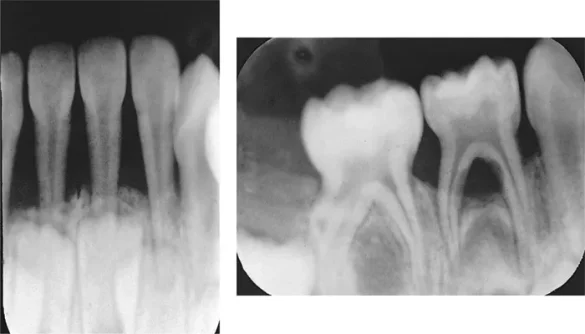

X-rays may be taken to assess the extent of bone loss around the teeth. If there is significant bone destruction, it is an indication that the disease has progressed to a severe stage.